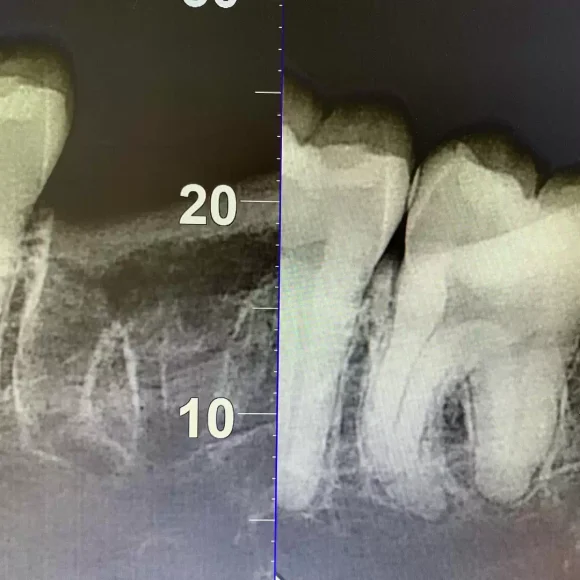

• При гингивите и пародонтите — способствует заживлению десны и восстановлению тканей пародонта.

• В имплантологии — помогает костной регенерации и повышает приживаемость имплантов.